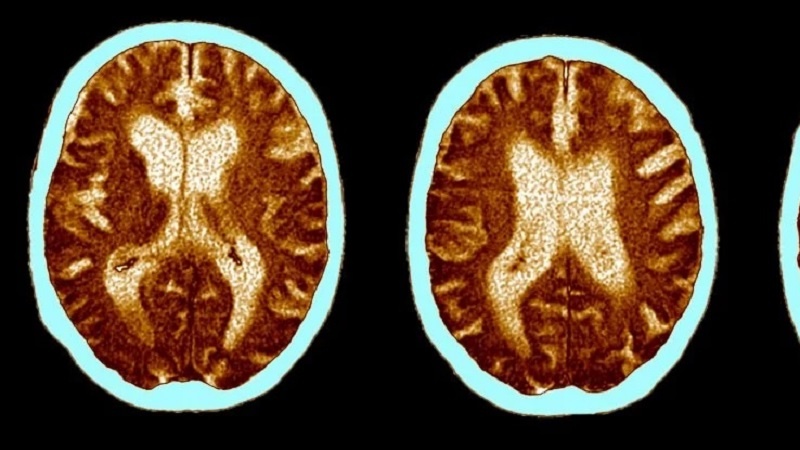

ROMA (Pars Today Italian) –– Dopo un anno dall’infezione da Covid-19 sono state riscontrate delle modificazioni del metabolismo del cervello,...

che hanno provocato nebbia mentale e disturbi di memoria e concentrazione. Tale situazione potrebbe anche essere legata ad un accumulo di molecole tossiche per i neuroni. Ciò è stato dimostrato in seguito ad una ricerca eseguita su sette pazienti, coordinata dall’Università degli Studi di Milano e condotta in collaborazione con il Centro Aldo Ravelli della Statale, l’Asst Santi Paolo e Carlo e l’Irccs Auxologico. I risultati dello studio sono stati pubblicati su Journal of Neurology. Il team di ricerca guidato dal neurologo Alberto Priori, ha esaminato sette persone che sono state ricoverate per Covid-19 e che a distanza di un anno dalle loro dimissioni mirati test neuropsicologici mostravano ancora disturbi cognitivi. I pazienti sono stati controllati utilizzando la metodica di tomografia a emissione di positroni (Pet) in grado di stimare l’attività metabolica di dettagliate aree del cervello e la deposizione di amiloide nello stesso. Il direttore della divisione di Medicina Nucleare e Radiodiagnostica dell’Asst Santi Paolo e Carlo, Luca Tagliabue, ha spiegato: “L’amiloide è una proteina che quando si accumula nei neuroni ne determina l’invecchiamento precoce e la degenerazione e che è implicata nella malattia di Alzheimer. Ebbene nel paziente esaminato la Pet ha rilevato un abnorme accumulo di amiloide nel cervello e particolarmente nei lobi frontali e nella corteccia cingolata, legate a funzioni cognitive complesse e alle emozioni”. Come riportato nello studio, l’aumento di amiloide nel cervello di un paziente, potrebbe innescarsi in base all’infezione o presentarsi in seguito all’infezione della cascata neurodegenerativa. Tuttavia, la certezza di questi dati dovrà essere accertata solo da nuovi studi, così da capire se l’infezione da Covid-19 possa più avanti provocare un aumento del rischio di malattie neurodegenerative. Infine, Vincenzo Silani, docente di Neurologia della Statale e direttore del Dipartimento di Neuroscienze dell’Irccs Auxologico, ha spiegato che: “Questo studio offre un ventaglio di ipotesi interpretative del danno post-Covid e pone le basi per una valutazione diversificata del paziente nel lungo termine. I processi neurodegenerativi potrebbero anche innestarsi post-infezione in casi selezionati secondo diverse vie patogenetiche e questa, ovviamente, è la domanda principale che ci poniamo: possiamo attenderci nel futuro patologie neurodegenerative?”.